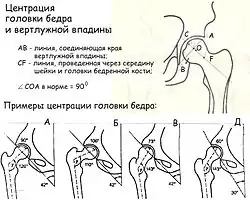

Очень важно соотношение между вертлужной впадиной и головкой бедренной кости. Для оценки геометрии тазобедренного сустава применяют много методов, один из них показан на рисунке. Важным показателем является центрация головки бедра и вертлужной впадины. Если провести линию через края вертлужной впадины (АВ) и линию через середину головки и шейки бедра (CF), то линия СF должна проходить через середину (точка О) линии АВ.

При этом угол, образованный этими линиями, должен приближаться к прямому. В этом заключается большой биомеханический смысл: равномерная нагрузка на головку и вертлужную впадину и нормальное развитие этих структур. Угол центрации тесно связан с формой шеечно-диафизарного отдела. В нижней части рисунка показаны некоторые формы дисплазии тазобедренного сустава, связанные с нарушением шеечно-диафизарного угла и угла наклона вертлужной впадины. Рисунок А – норма. Линия наклона вертлужной впадины и срединная линия головки и шейки составляют прямой угол, ШДУ и угол наклона вертлужной впадины не изменены. Рисунок Б – варусная деформация проксимального отдела бедра с нарушением центрации. Рисунок В показывает форму дисплазии с увеличением ШДУ при нормальном угле наклона вертлужной впадины. Рисунок Д – дисплазия, при которой сочетается избыточный ШДУ и избыточный угол наклона вертлужной впадины[12].